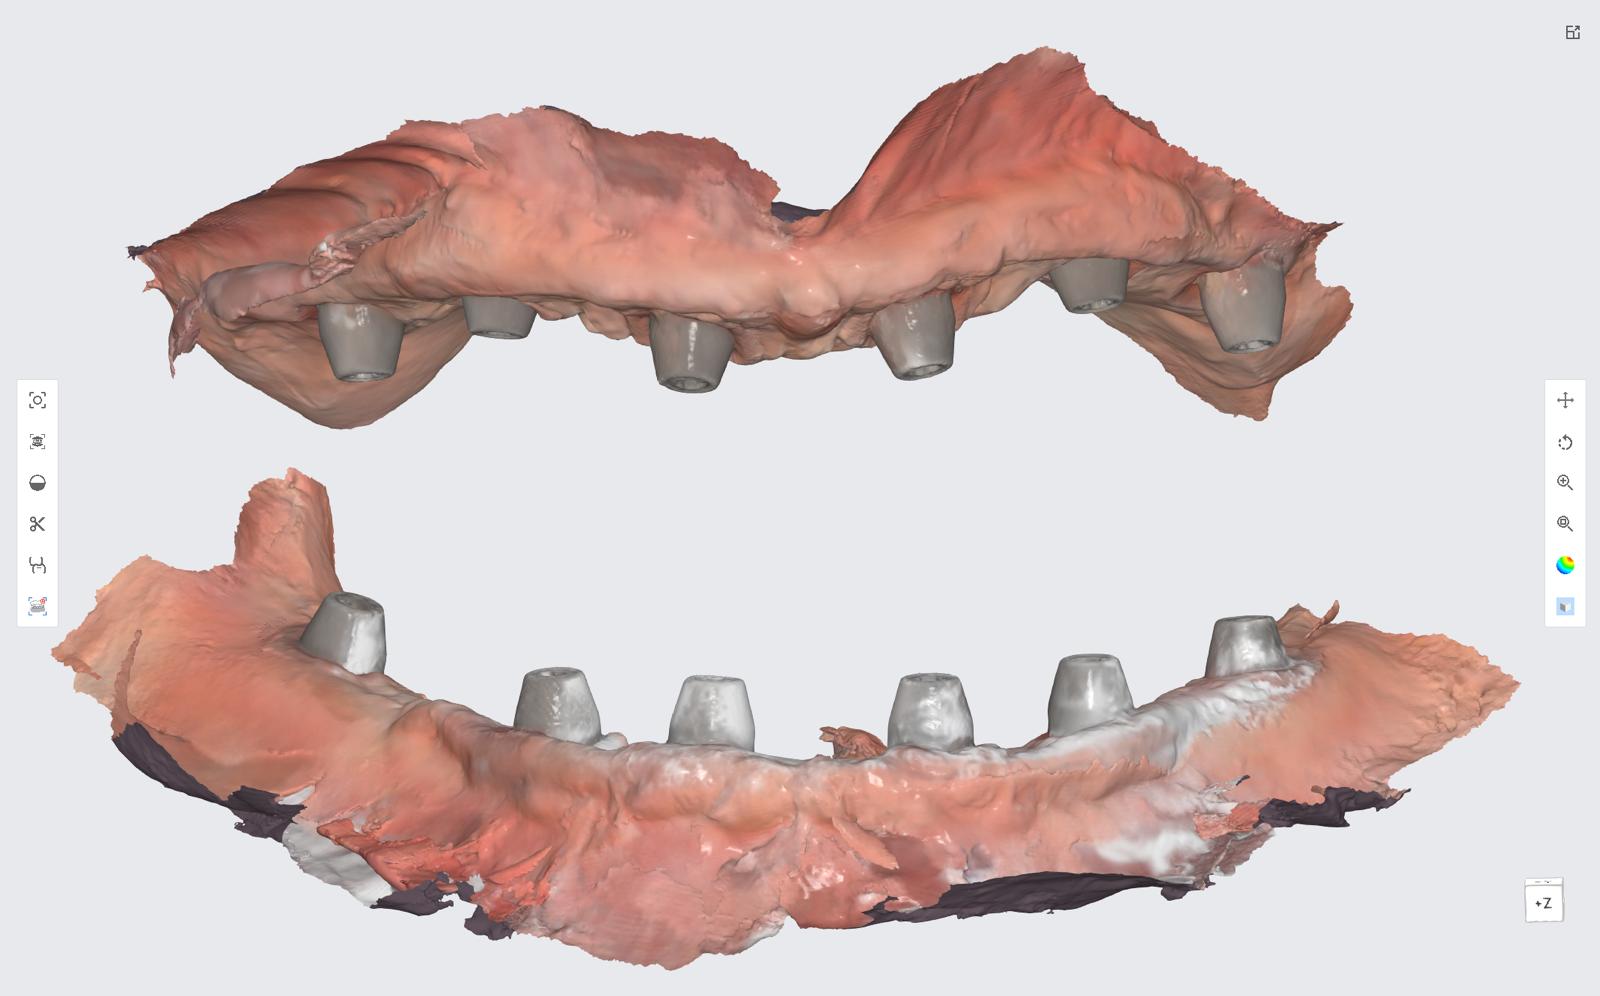

The revolutionary All-on-X (AOX) model-less workflow has become a reality through seamless integration of state-of-the-art technologies: interactive implant planning software, guided surgery systems, intraoral scanning (IOS), advanced 3D printing, and photogrammetry. Our innovative CAD-CAM protocols dramatically streamline the treatment process, reducing appointment frequency, chair time, and prosthetic delivery intervals. We've pioneered multiple digital workflows that ensure precise implant position recording and bite capture for full-arch implant rehabilitation.

- Master comprehensive digital workflows incorporating AI Smile Design, facial scanning, intraoral scanning, photogrammetry, Exocad design, and cutting-edge 3D printing and milling technologies

- Master new digital techniques for capturing implant positions with absolute precision